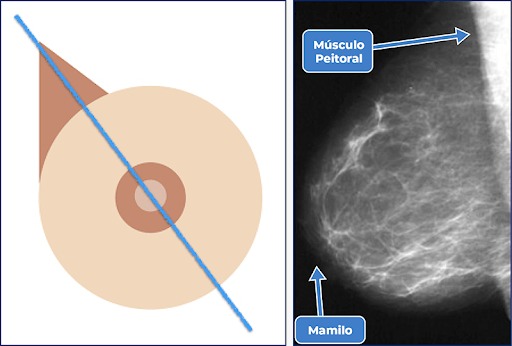

Transforme vidas

70% vai para a Rede de Olho no Câncer — em prol do Centro da Mama · 30% para custos e reposição.